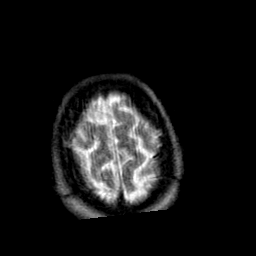

Creutzfeld-Jakob disease: T2-weighted MR -- Slice #21

[Home][Help][Clinical] Slice 21